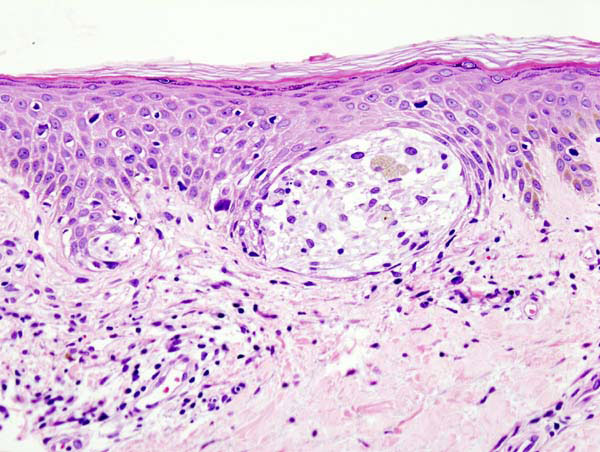

該研究觀察了98個人類黑色素細胞病變(男性和女性的原發(fā)性和轉(zhuǎn)移性黑色素瘤)。幾乎所有樣本都表達了大量的ZIP9,而在其中任何一個樣本中都檢測不到雄激素受體。